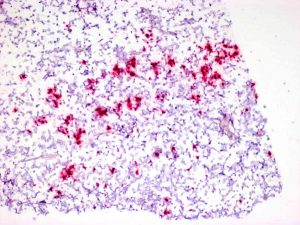

当HIV-1进入大脑时,它靶向小胶质细胞,神经系统的哨兵免疫细胞。感染的小胶质细胞破坏了大脑并引起神经变性(神经元的渐进病)和痴呆。